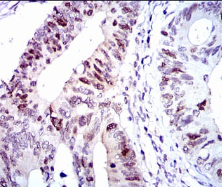

IHC    1/200 - 1/1000